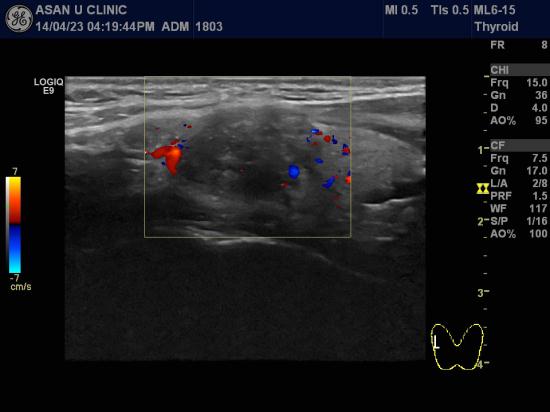

30세 여성분입니다.

4년전쯤 갑상선에 혹이 있다는 이야기를 기억하여

검사하러 오셨읍니다.

양측 갑상선에 결절들이 여러개 있었고

오른쪽 턱밑과 경동맥의 혈관따라,

왼쪽 경동맥 혈관따라 여러개의 림프절이 비대되어 있었고

미세석회화소견도 함께 보였습니다.

흡인세침검사를 실시하여

양쪽 갑상선에 유두암과 양쪽 목부위 림프절의 전이로 각각 진단되었습니다.